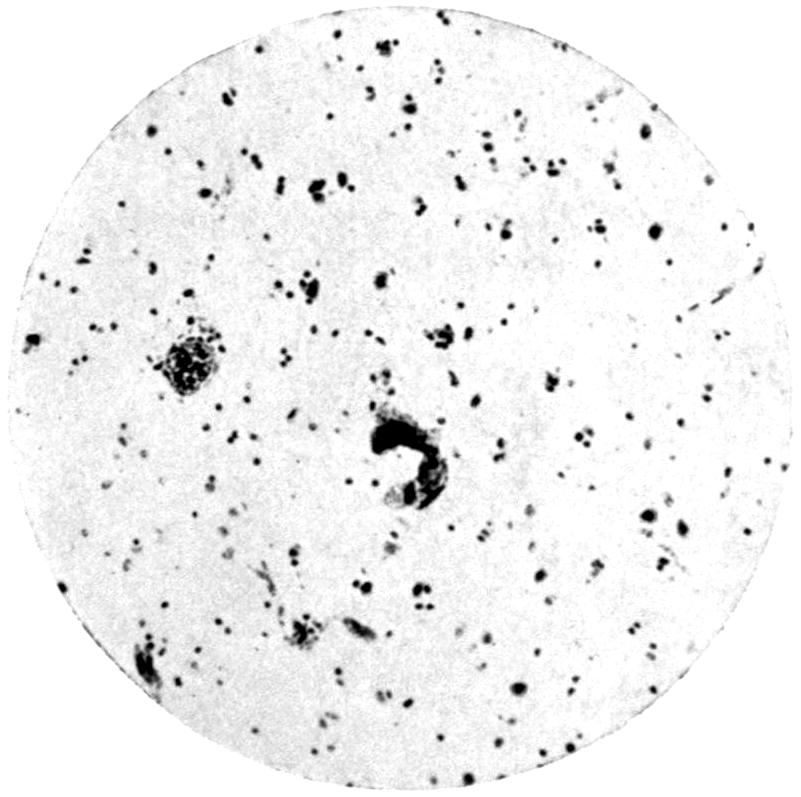

Plate I. 92